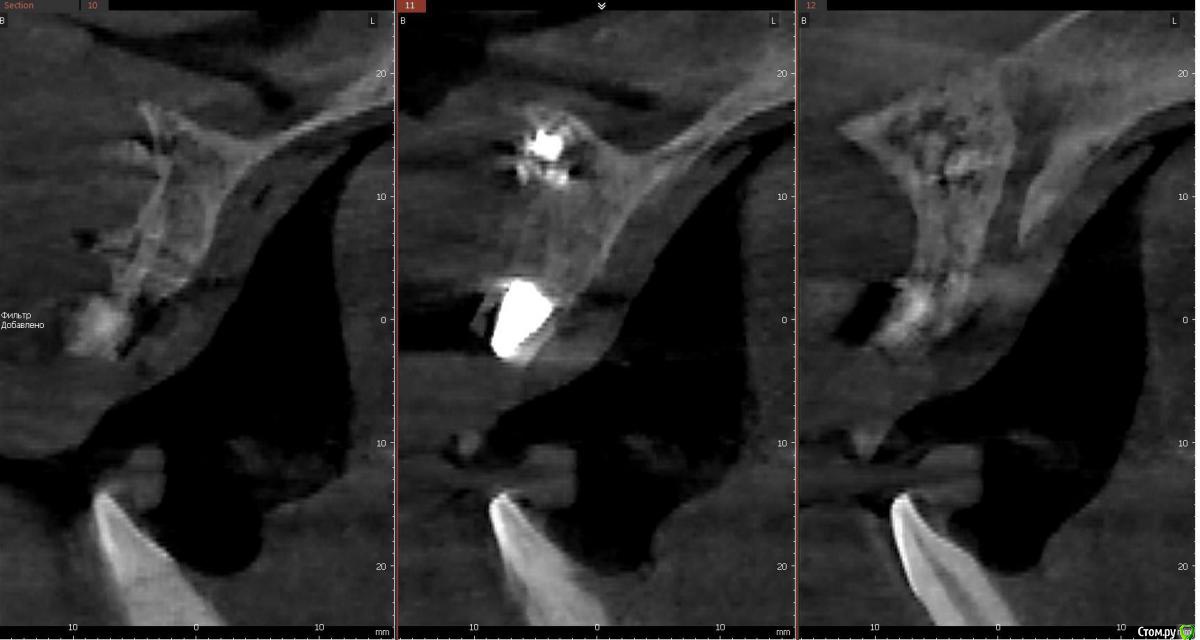

колесников Опубликовано 21 апреля, 2018 Поделиться Опубликовано 21 апреля, 2018 (изменено) Расширяем показания. В первом случае пациент наотрез отказался расставаться с коронковой частью зуба. Проведена консервация ,корень 25 удалён до круговой связки ,коронка установлена в лунку и фиксирована композитной шиной,из прикуса выведена. (25,26 позднее сделаю одномоментно). Итог не очень. Ввиду отсутствия болевых ощущений ( жирный плюс метода) пациент жевал без ограничений,шина откололась на 4ый день и он самостоятельно все разобрал. На момент осмотра лунка регенерирована на 2/3. ( фото нет,был расстроен). Идея мне понравилась,при случае ещё раз воспроизведу,но шинирую поосновательней.Второй случай. Одномоментная имплантация 36. Имплант с небольшим торком,пациент уезжает . Как закрыть лунку,сохранить графт и десневой контур? Для индивидуального формирователя не был заказан временный абатмент. Поверх формирователя высотой 3мм,оставил латку из радикса по форме лунки и фиксировал композитом. (Формирователь докрутил). Вид через 3 дня. Первичными результатами доволен,буду практиковать. Изменено 21 апреля, 2018 пользователем колесников 2 Ссылка на комментарий